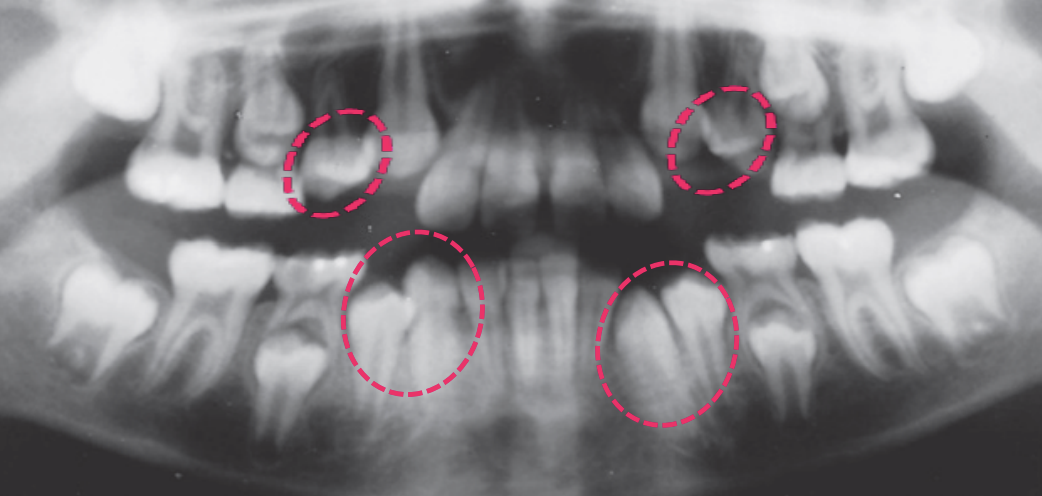

The age in this picture is characterized by the teeth erupted which are: Maxilla ABCDE and Mandible ABCDE. The teeth unerupted are the Maxilla 1234567 and the Second molar in the Maxilla- 1/3 Crown completed, Mandible- 1/3 crown completed

The age in this picture can be estimated by the erupted teeth which are: Maxilla ABCDE, Mandible ABCDE. The unerupted teeth are the Maxilla 1234567 and, Mandible 1234567 and the main identifying feature is the Second molar – Maxilla- 2/3 Crown completed, Mandible- 2/3 crown completed

At age 6 is characterized by the erupted first molar in the maxilla, and the erupted central incisor and first molar in the mandible. Teeth erupted – Maxilla ABCDE6, Mandible 1BCDE6 - Teeth unerupted – Maxilla 123457, Mandible 23457

Dental age 7 is characterized eruption of permanent teeth Mandibular Lateral Incisor, Maxillary Central Incisor

Dental age 8 is characterized by eruption of the maxillary lateral incisors

Teeth erupted – Maxilla 12CDE6, Mandible 12CDE6

Teeth unerupted – Maxilla 3457, Mandible 3457

Dental age 9 the maxillary lateral incisors have been in place for 1 year, and

root formation on other incisors and first molars is nearly complete.

Teeth erupted Maxilla 12CDE6, Mandible 12CDE6